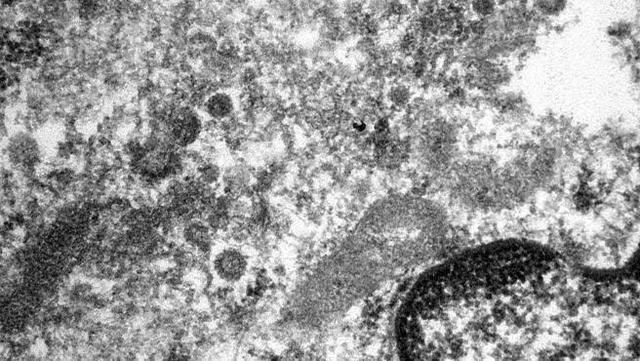

西班牙一家医院制作出新冠病毒在患者细胞中的显微照片

当地时间4月29日,据西班牙当地媒体报道,西班牙巴塞罗那的一家综合性医院制作出新型冠状病毒在患者细胞中的电子显微照片。该显微照片将实体放大了34000倍,照片显示出位于患者血管内的内皮细胞的细胞核和部分细胞质,冠状病毒主要在细胞质中繁殖,并扩散至机体的其余部分,冠状病毒的感染始于病毒体与宿主细胞受体的结合,随后通过胞吞作用进入人体细胞。